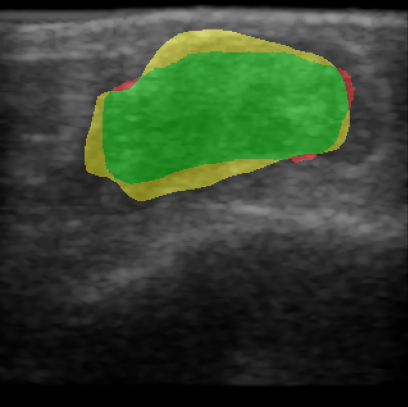

For quantitative evaluation of the network, we calculated precision, recall and the Dice score, also known as F1 score, of the network prediction compared to the GT annotation. Results are also visualized to compare GT with the network prediction. True positive (TP) pixels are colored green, false positives (FP) are colored yellow, false negatives (FN) are colored red and true negative (TN) areas are transparent.

To better understand the wound morphology and how its composition relates to measured US intensities, we analyze the average US intensity in different sections of the wound for all scans of the test set. The wound area is given by the GT segmentation mask for each scan. We introduce an evaluation scheme that adapts the segmented wound area by a dilation and erosion process. We calculated the ratio of the mean US intensity m¯rsubscript¯𝑚𝑟\overline{m}_{r} of different wound regions compared to m¯wsubscript¯𝑚𝑤\overline{m}_{w} over the whole wound. We used the regions 0–50\ts\ts\ts% (blue), 50–75\ts\ts\ts% (orange), 75–100\ts\ts\ts% (green) and 100–120\ts\ts\ts% (red) of the actual wound area. Figure 1 shows the different wound regions.

Refer to caption

Figure 1: Different wound regions for comparison of US intensities m¯rsubscript¯𝑚𝑟\overline{m}_{r} within the wound.